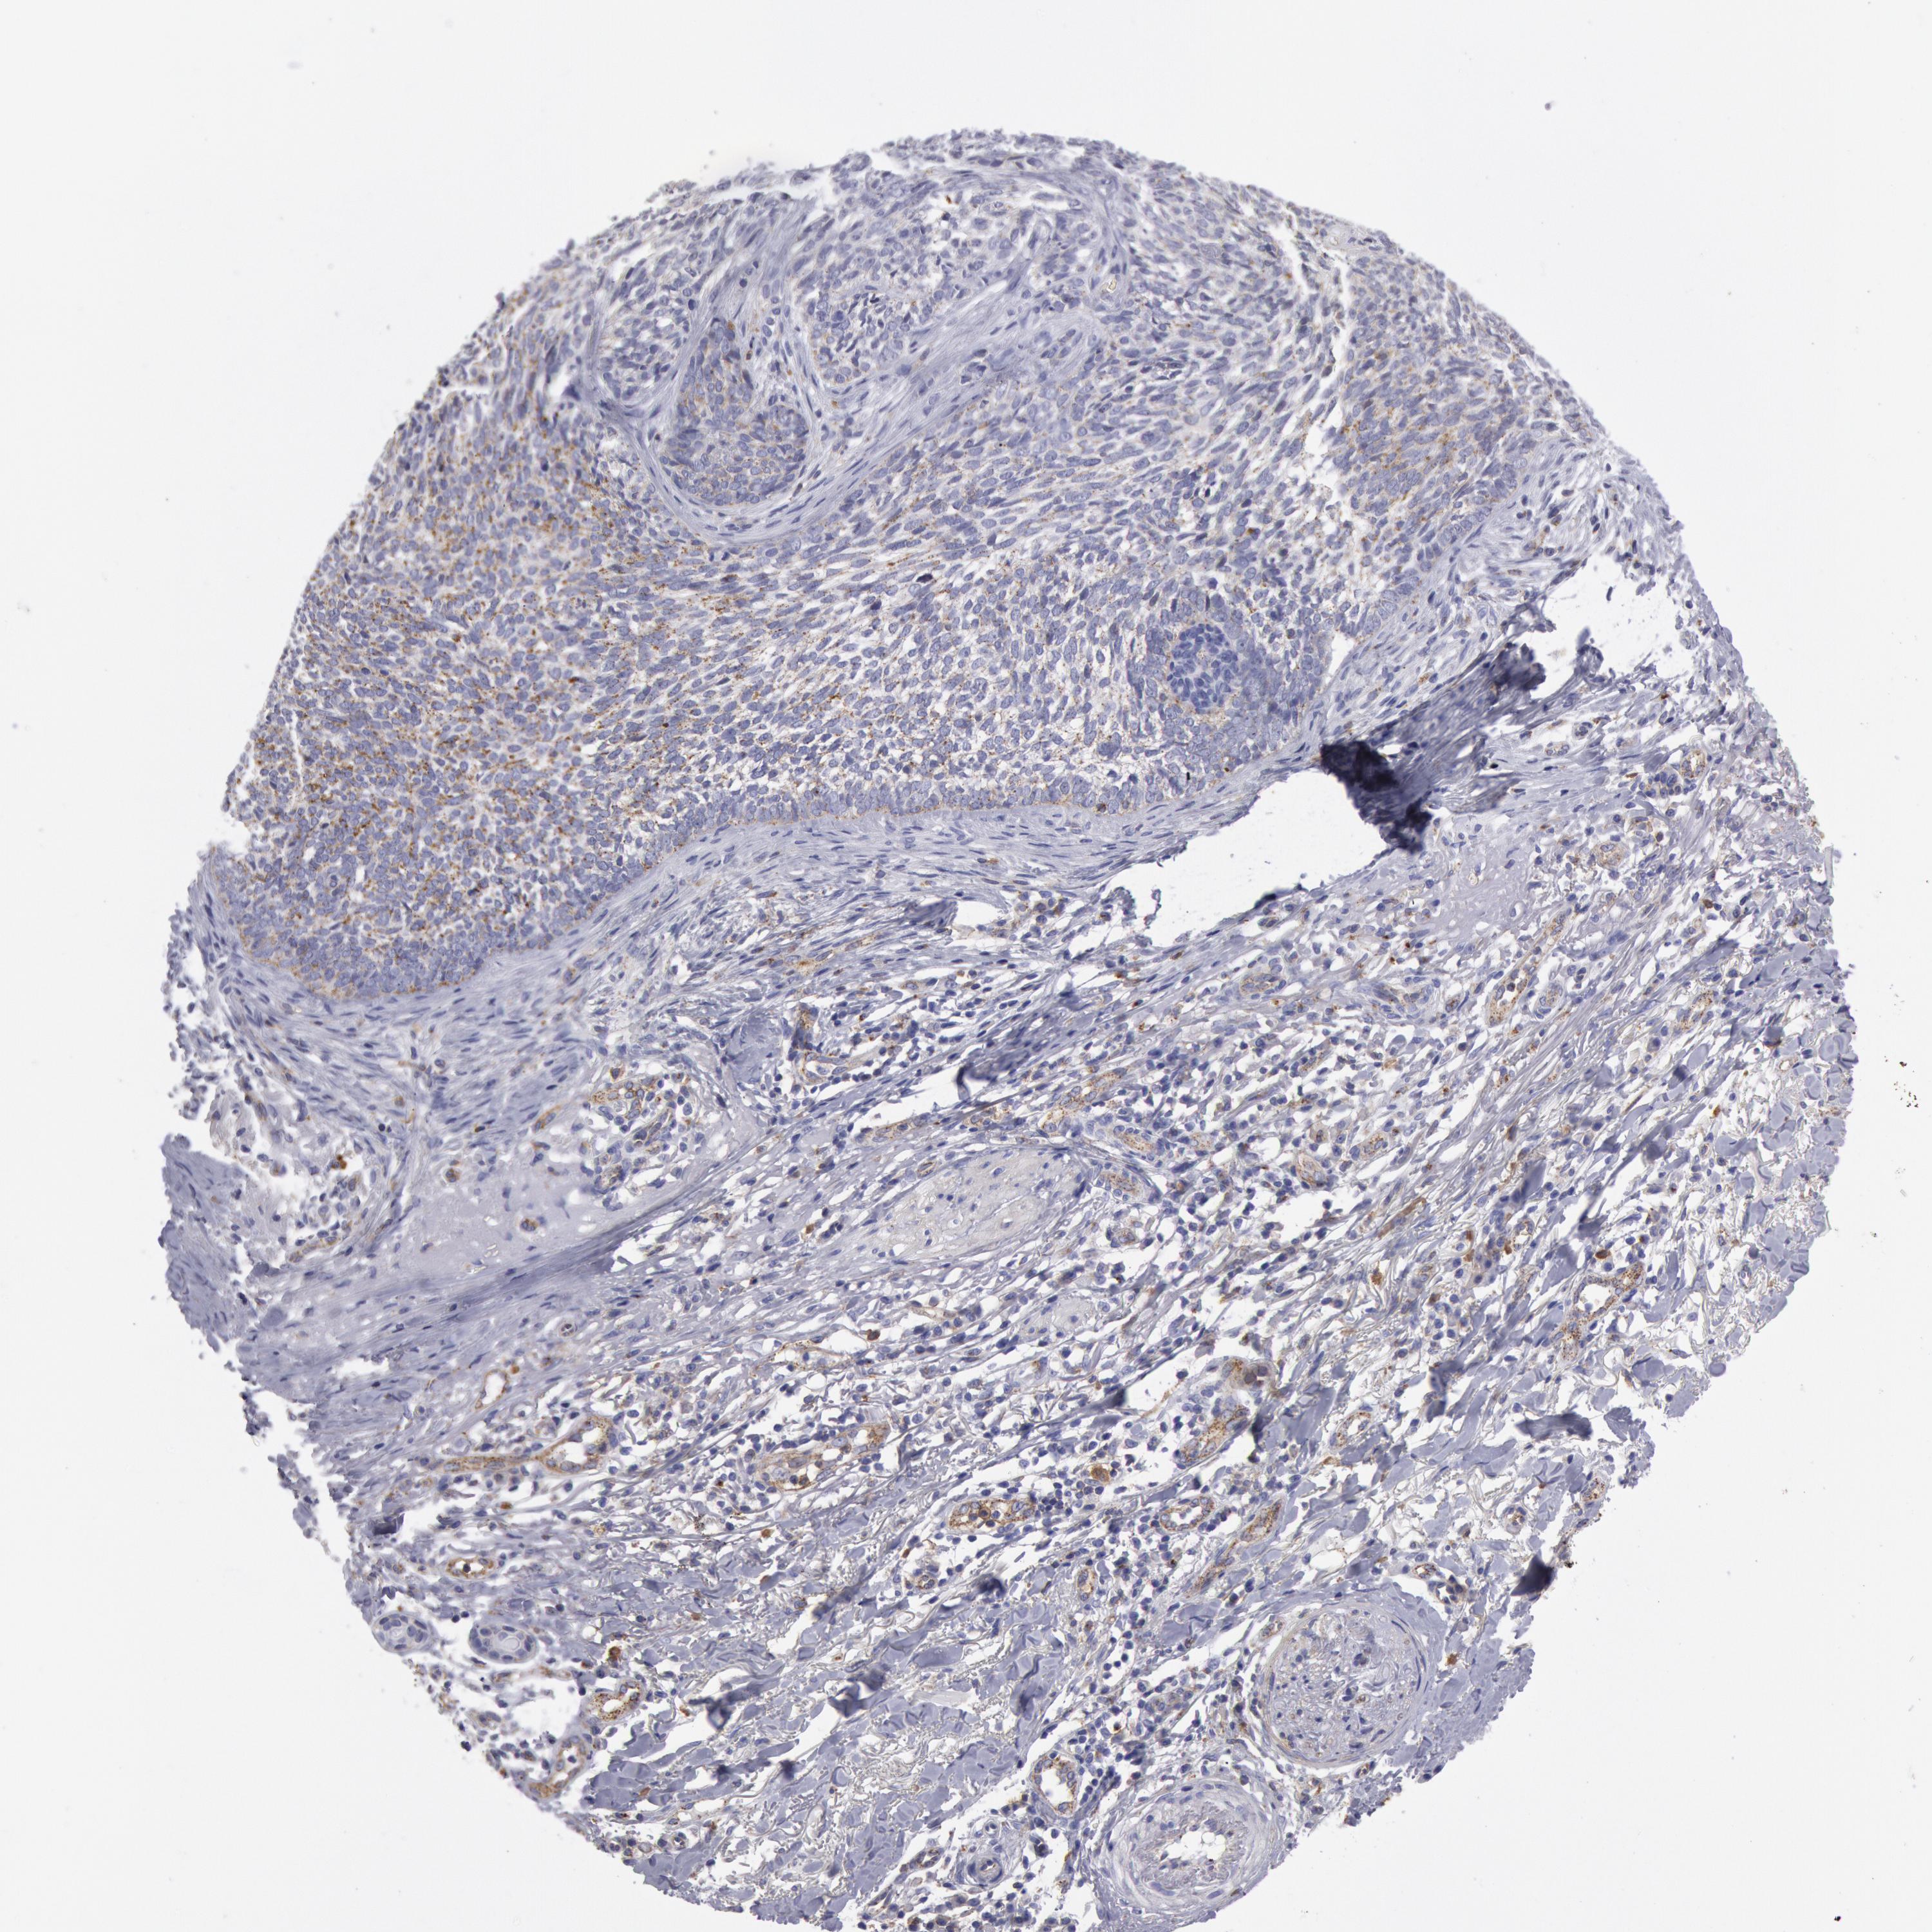

SKIN CANCER - Protein expressioni

A mouse-over function shows sample information and annotation data. Click on an image to view it in a full screen mode. Samples can be filtered based on level of antibody staining by selecting one or several of the following categories: high, medium, low and not detected. The assay and annotation is described here.

Antibody stainingi

Antibody staining in the annotated cell types in the current human tissue is reported as not detected, low, medium, or high, based on conventional immunohistochemistry profiling in selected tissues. This score is based on the combination of the staining intensity and fraction of stained cells.

Each image is clickable and will lead to virtual microscopy that enables deeper exploration of all samples and also displays staining intensity scores, fraction scores and subcellular localization as well as patient and tissue information for each sample.

Antibody CAB007766

Basal cell carcinoma

Squamous cell carcinoma, NOS